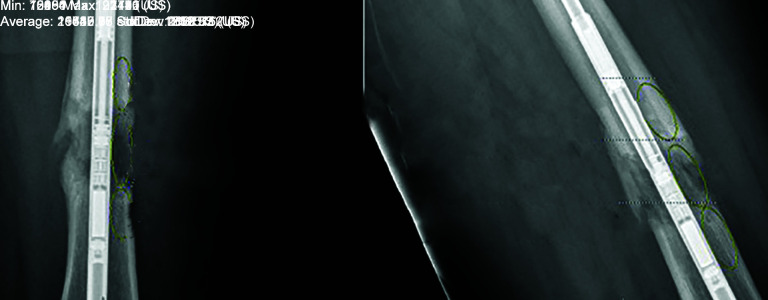

Methods: A retrospective review identified 13 patients (13 nails) who underwent femoral lengthening using the fitbone and 14 patients (16 nails) lengthened with the precise. Patients were matched for age, sex, aetiology and length achieved.Regenerate analysis was undertaken using the pixel ratio value (PVR), calculated on the radiographs when at the desired length, followed at 4, 8, and 12 weeks. The mean of the two highest ratio values were also assessed, as an indicator that full weight-bearing would be permitted. Complications were recorded in relation to bone, soft tissues and implant.

Results: Seven males and 6 females underwent 10 antegrade and 3 retrograde fitbone lengthening. Nine male and 5 female underwent 14 antegrade and one retrograde precise lengthening. The mean age at surgery was 36 years in both groups. Mean length in the fitbone group was 41.7, and 46.8 mm in the precise group. All except one fitbone patient reached the desired length (6 mm short). The regenerate fully consolidated in all patients.There was no statistical difference between the PVR measurements of the cortices at any time interval. There was no difference seen in the time for full weight-bearing or a difference seen in the mean PVR measured at this particular time. There were complications seen in the fitbone group including bolt migration, premature consolidation, and soft tissue irritation from the antenna requiring early surgical removal. There were no complications recorded in the precise group.